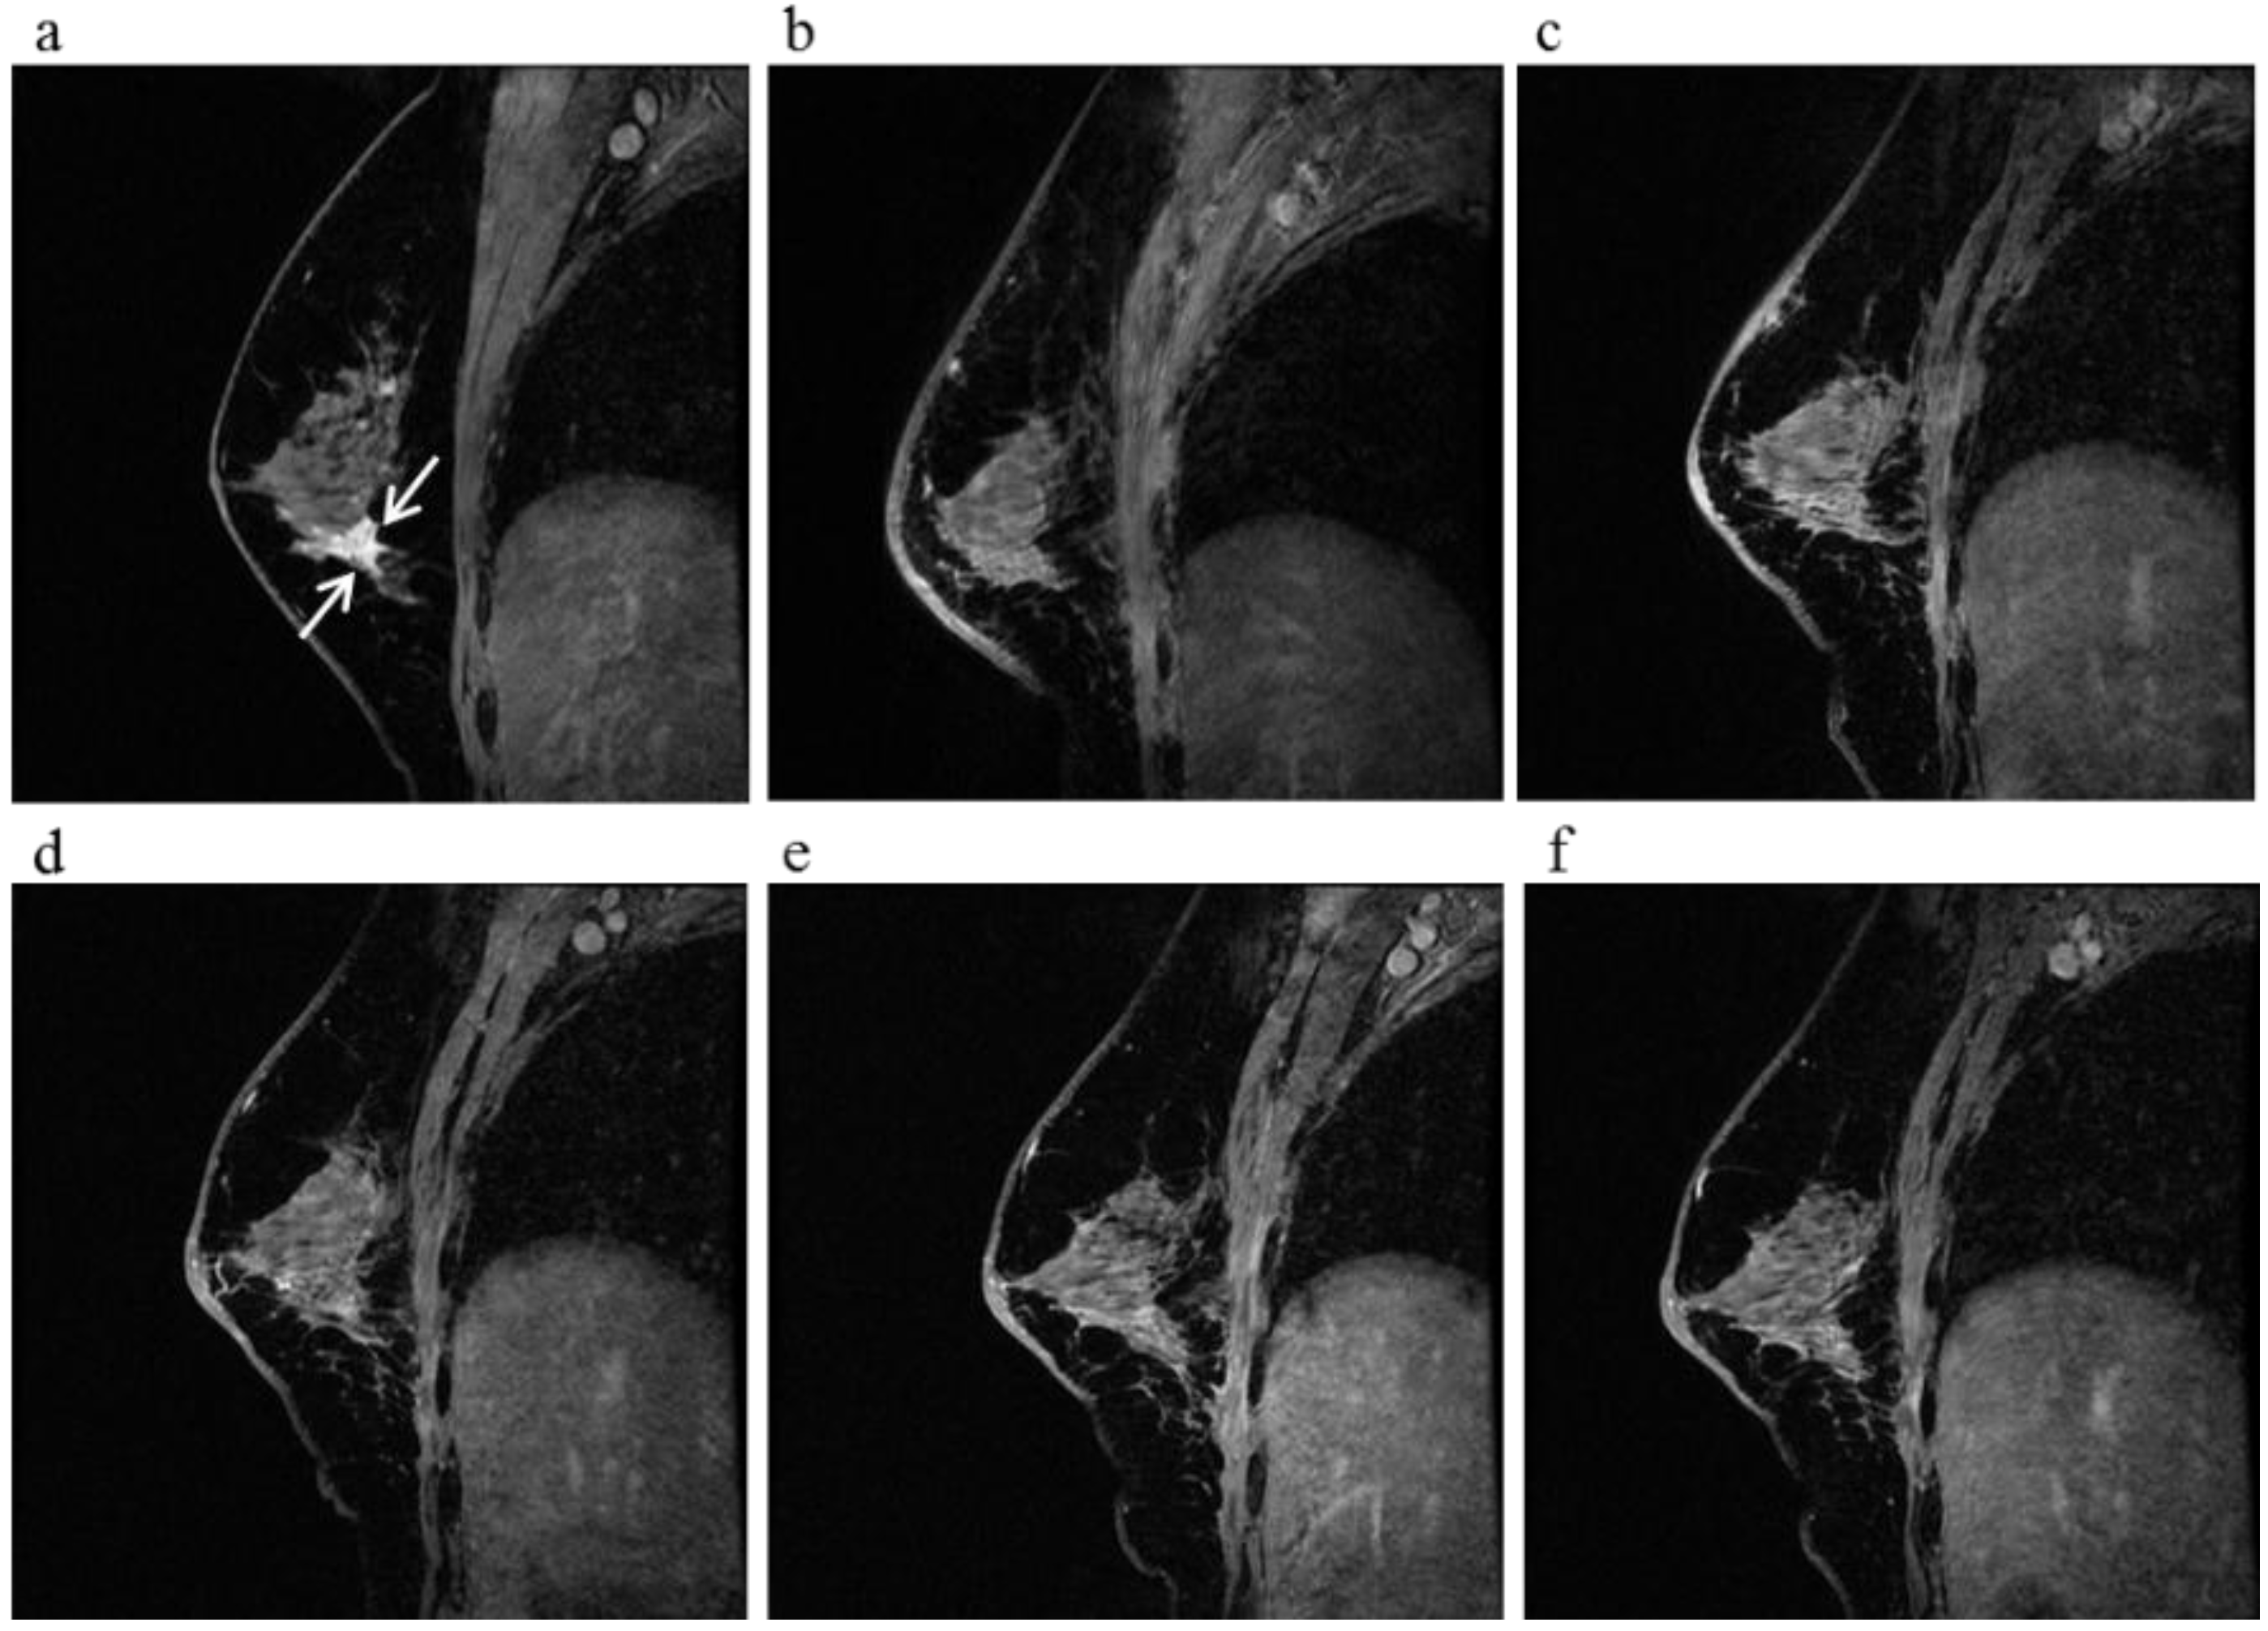

Figure 2.

A 64-year-old female (case 3 in Table 1, Table 2 and Table 3) with left breast cancer (cT2N0M0). CE breast MRI, PET-CT and mammography revealed a breast tumor before KORTUC II therapy, the region of tumor was >20 mm (a–c). After the completion of KORTUC II, the tumor disappeared on the serial examination ((d–f): initial examination after KORTUC II treatment, (g–i): final examination), and no recurrence was identified. The findings of CE breast MRI seems to be most reliable among these three diagnostic modalities in terms of recognition of tumor disappearance.